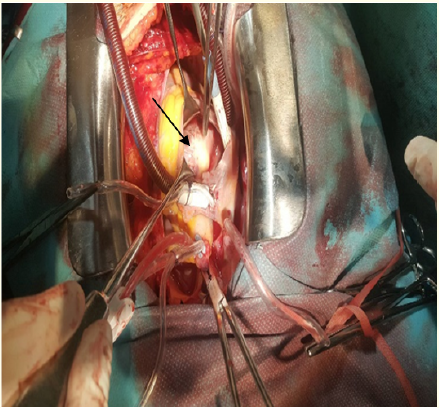

Cardiac Hydatid Cyst of the Interventricular Septum Complicated by 03rd Degree Atrioventricular Block in a Pregnant Woman: A Case Report

Lakehal Redha, Khacha Khaled, Babouri Abdelrahman, Bendjaballah Soumaya, Aziza Baya and Bouzid Abdelmalek. 5(10): 46-50.